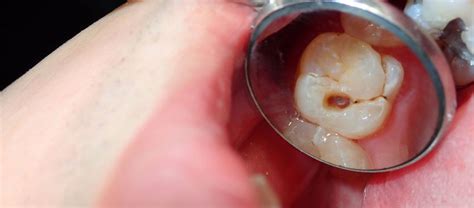

- Inspección Visual: El primer paso para detectar la caries es observar de cerca los dientes. Para ello, el dentista utiliza un pequeño espejo y una luz muy brillante. Durante este primer examen, el médico puede detectar cambios en la superficie del diente que pueden indicar la presencia de caries.

- Caries Oclusal: Se trata de la caries que se forma en el diente, es decir, en las superficies masticatorias de los molares.